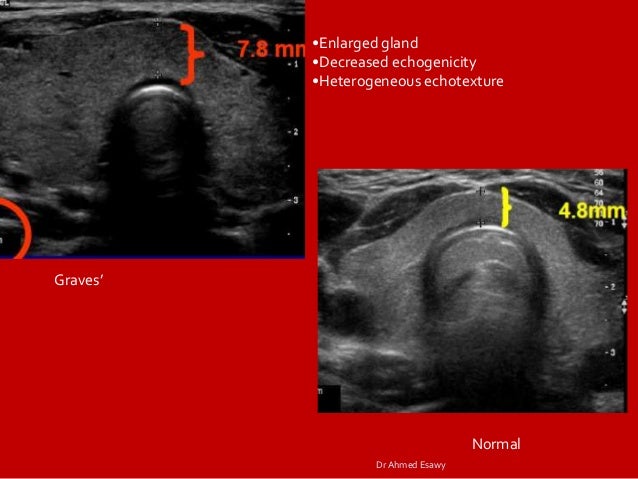

Thyriod Gland Imaging Part 2 Full Story Diffuse Thyriod Disease Dr

Presentation1 Pptx Radiological Imaging Of The Thyroid Gland Disease